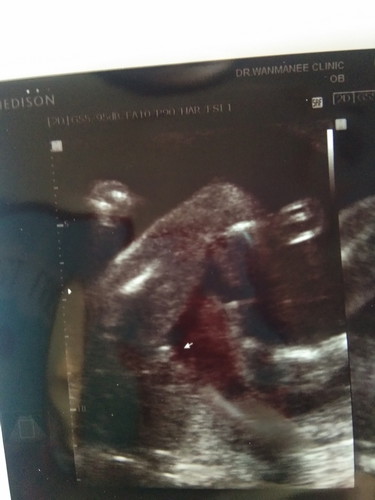

ลูกชายหรือลูกสาว

หมอบอกว่าลูกสาวเหมือนมันนูนๆตรงกลาง แม่ๆช่วยคอนเฟริมหน่อยค่ะไม่กล้าชื้อของไว้รอ

น่าจะลูกสาวค่ะแม่ ถ้าลูกชายจู๋จะโผล่ชัดเจนมากเลยค่ะแม่

ตั้งครรถ์